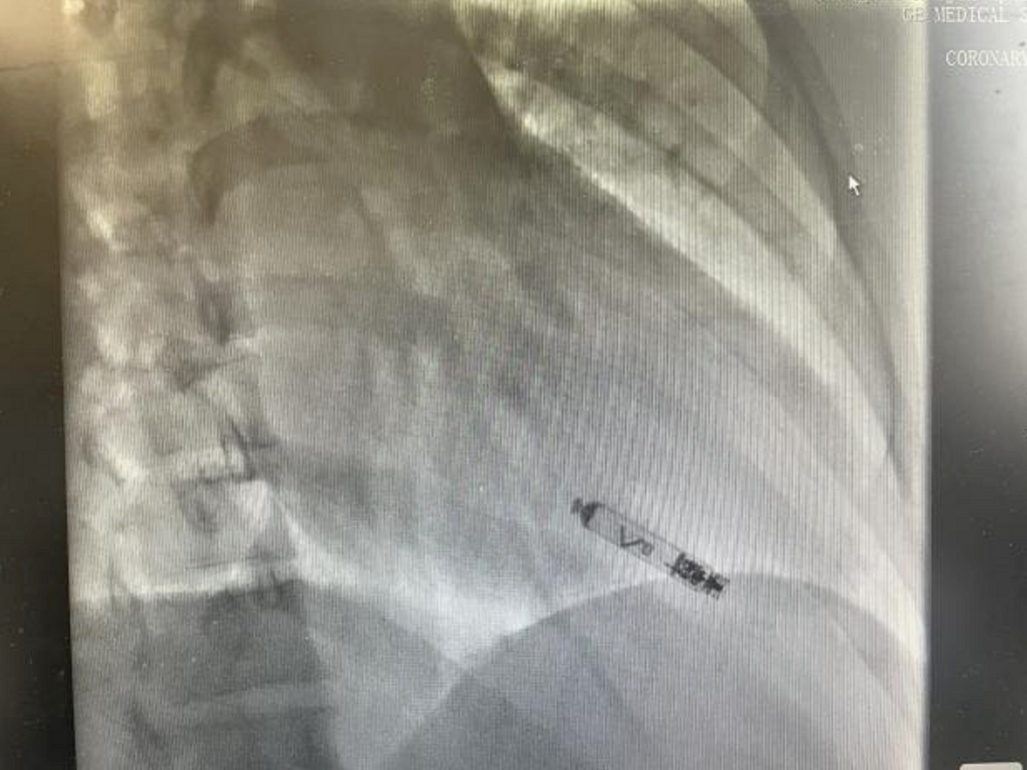

与传统的心脏起搏器治疗方式不同,无导线起搏器具有显著优势。传统治疗中,患者需要在体内植入一个脉冲发生器和多根电极,而无导线起搏器体积微小,仅有传统起搏器体积的十分之一,外形宛如一粒胶囊。它通过股静脉经导管置入心脏,操作简单且安全可靠。在此次手术中,从穿刺到释放仅用时40分钟,术程十分流畅,起搏器一次成功释放,郑女士在术中没有明显不适,术中术后电学参数均保持良好。由于无需建立囊袋且没有导线,该术式有效避免了囊袋感染的风险,减少了导线引发的三尖瓣反流等并发症,同时不会对患者肢体活动造成限制,大幅缩短了术后恢复时间。

术中,邱筱炜副主任医师团队严格按照标准植入流程进行操作,各项参数均符合要求,成功完成了手术植入。这一新技术为郑女士带来了诸多实实在在的益处。术中可实时监测参数,在旋入前标测电学参数,实现精准固定,显著降低了手术风险及心肌损伤的可能性。国外相关数据表明,约一半使用主动螺旋起搏器的患者使用寿命超过20年,这意味着郑女士后期更换起搏器的次数将大幅减少。而且,主动螺旋固定且配有专用取出鞘管的设计,使得起搏器电池耗竭后能够按需安全取出。此外,基于郑女士的疾病进展情况,未来还可按需升级为更加生理的真实双腔无导线起搏器,为她的健康提供了更长远、更全面的保障。